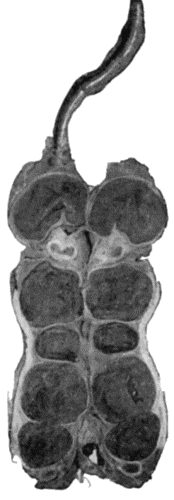

118.Shaft of the Femur after Acute Osteomyelitis 444

119.Femur and Tibia showing results of Acute Osteomyelitis 445